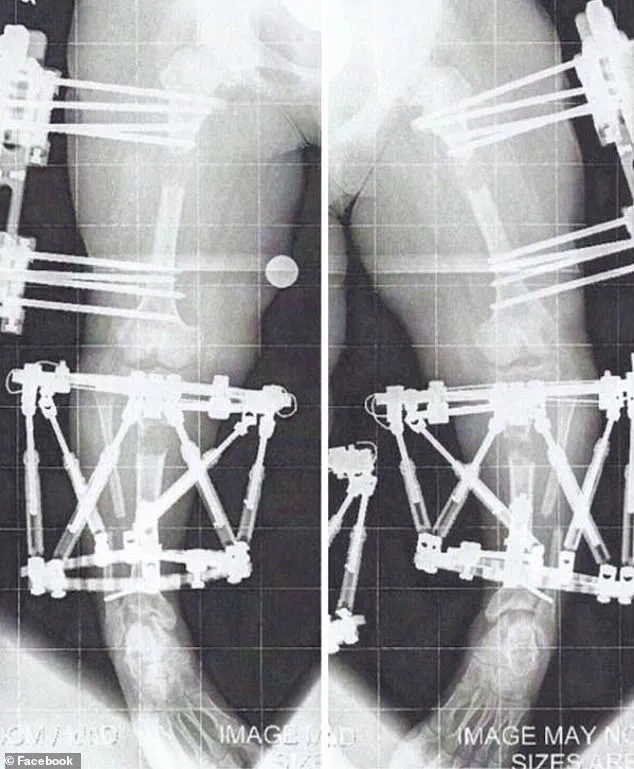

The procedure, which involves extending bones by approximately 1 millimeter per day during the 'distraction phase,' is a testament to both medical innovation and the relentless pursuit of physical normalcy.

After the desired length is achieved, the device—whether an external fixator or internal rod—is removed, and the new bone is left to fuse back together.

The initial post-surgery recovery from Crews' first procedure was grueling.

It involved two to three hours of personal training sessions five days a week, along with daily exercises and stretches, all done in her own time.

By the time the fixators were removed from her first leg in April 2011, the physical and emotional toll was immense.

She recalled the period after removal as one month of no weight-bearing, followed by a painstaking re-learning of how to walk.

Using a walker for two weeks, then quad canes for another, she eventually transitioned to unassisted walking by June.

Her arm lengthening procedure, which involved fixators implanted in January 2012 when she was 17, was less restrictive than her leg surgeries, as the fixators were limited to her humerus, allowing her to remain mobile during the process.